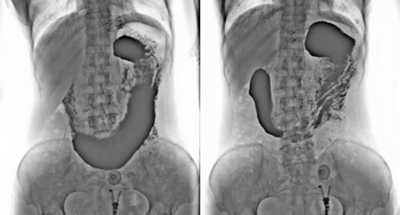

3. 數(shù)字化胃腸:

★消除普通數(shù)字胃腸機視野小的缺陷,直接獲得大視野全數(shù)字化圖像 (17x17) 。

★更加方便胃腸、食管、上消化道、全消化道等造影功能!

★通過動態(tài)攝影觀察組織器官的功能運行情況,并輕松進行點片拍攝。

★各種普通及特殊造影,如口服膽囊造影、靜脈膽道造影、T管造影、逆行胰膽管造影(ERCP)、靜脈腎盂造影(IVP)、子宮輸卵管造影、脊髓造影等。